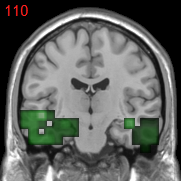

Figure 1: The overlapped voxels among top 150 negative value voxels in each fold of βpresubscript𝛽𝑝𝑟𝑒\beta_{pre} at the time corresponding to the best average prediction result in the path of GSplit LBI using 10-fold cross-validation. For subjects with AD, they represent enlarged GM voxels surrounding lateral ventricle, subarachnoid space, edge of gyrus, etc.

The process of feature selection combined with prediction accuracy can be analyzed together along the path. The result of 30ADNC is used as an illustration in Fig. 3. We can see that βpresubscript𝛽𝑝𝑟𝑒\beta_{pre} (blue curve) outperforms βlessubscript𝛽𝑙𝑒𝑠\beta_{les} (red curve) in the whole path for additional procedural bias captured by βpresubscript𝛽𝑝𝑟𝑒\beta_{pre}. Specifically, at βpresubscript𝛽𝑝𝑟𝑒\beta_{pre}’s highest accuracy (t5subscript𝑡5t_{5}), there is a more than 8%percent88\% increase in prediction accuracy by βpresubscript𝛽𝑝𝑟𝑒\beta_{pre}. Early stopping regularization at t5subscript𝑡5t_{5} is desired, as βpresubscript𝛽𝑝𝑟𝑒\beta_{pre} converges to βlessubscript𝛽𝑙𝑒𝑠\beta_{les} in prediction accuracy with overfitting when t𝑡t grows. Recall that positive (negative) features represent degenerate (enlarged) voxels. In each fold of βpresubscript𝛽𝑝𝑟𝑒\beta_{pre} at t5subscript𝑡5t_{5}, the commonly selected voxels among top 150 negative (enlargement) voxels are identified as procedural bias shown in Fig. 1, where most of these GM voxels are enlarged and located near lateral ventricle or subarachnoid space etc., possibly due to enlargement of CSF space in those locations that are different from the lesion features.